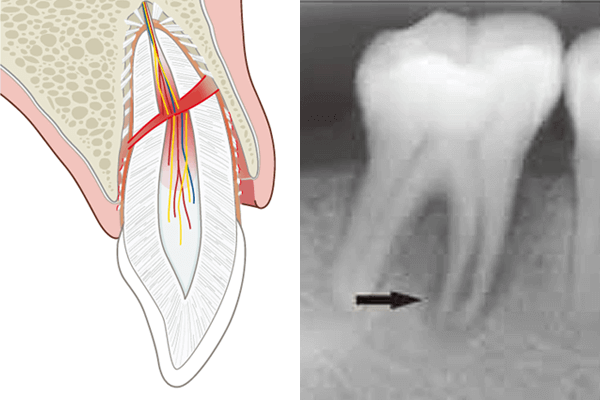

歯が真ん中よりも根っこに近い部分で折れた場合は、神経が露出する場合が多く、残念ながら神経を取らないといけない事が多いです。(ただ、神経はなるべく取らない方が良いので当院ではなるべく残す様努力しています)

神経を取ったら、歯の内部を消毒し、そこに薬を詰めます。

▲残った神経を除去し、中を消毒した後に、薬を詰めた様子

薬を詰めたら、そこに土台を入れます。そして、その上からすっぽりと歯をかぶせます。